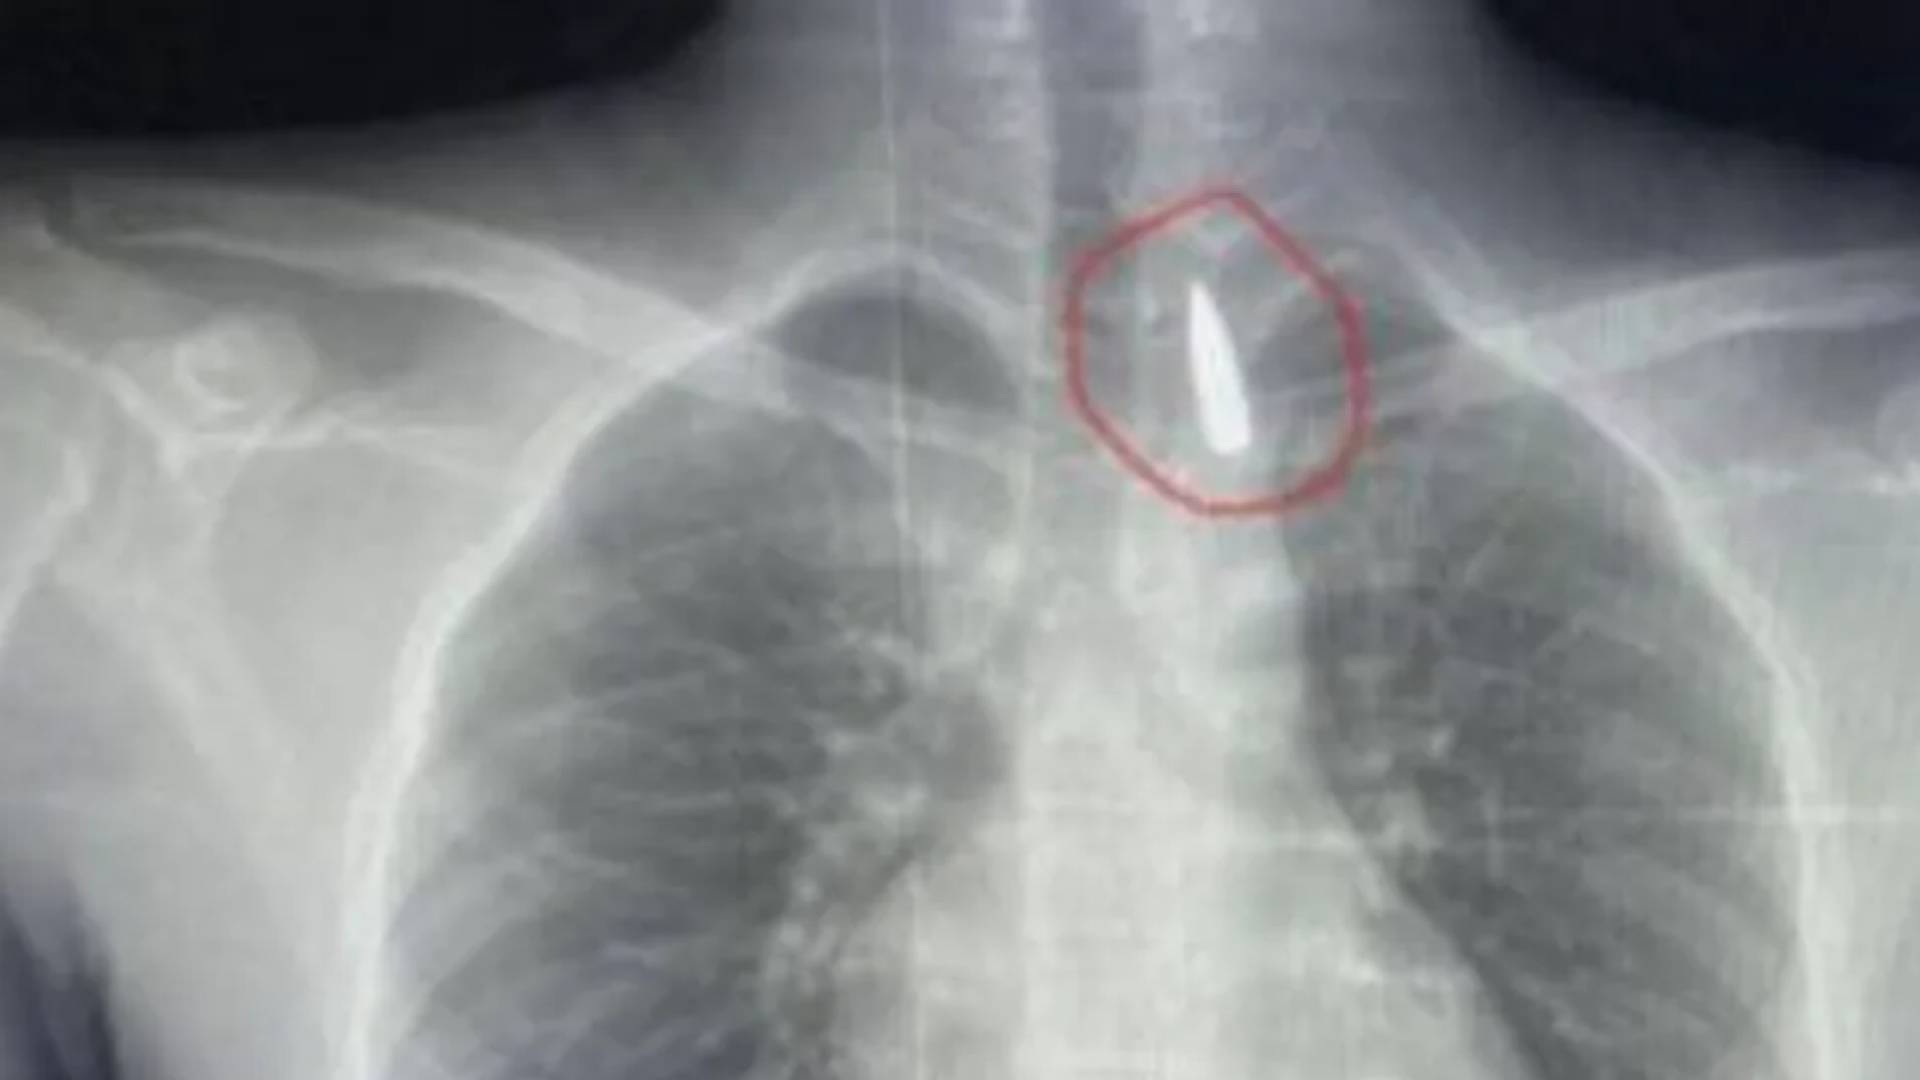

صورة أشعة توضح أين استقر المقذوف الناري

من "إنجاز طبي" إلى "رسالة دولة" الحدث الطبي، الذي تمثل في نجاح فريق جراحة القلب والصدر بمستشفيات جامعة الإسكندرية في استخراج مقذوف ناري استقر قرب الشريان الأورطي لمصاب من غزة، كان هو المنصة التي انطلقت منها الرسائل السياسية.

التفاصيل الطبية، كما أوردها عميد كلية الطب تامر عبد الله، تبرز التعقيد الشديد للحالة، حيث أن أي خطأ كان يعني الوفاة الفورية.